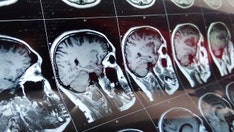

Scientists at the University of Cambridge discovered that dementia patients often showed poor signs of cognitive and physical health years before their diagnosis. (iStock)